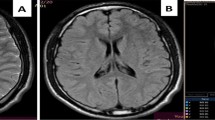

There were, on the T1-weighted and FLAIR images, multiple, abnormal, high intensity signal lesions in centra ovale, corpus callosum (splenium), and pons white matter, which were hypointense on T2* sequences (see Fig. 4). These data suggested a magnetic susceptibility effect of methaemoglobin. We drew on the DTI b0 images two ROIs of 88 mm2 (25 pixels), one on the patient’s abnormal corpus callosum (splenium) area that matched the abnormal one in FLAIR and one on the normal part of the splenium. The ADC values were increased (1.11±0.03×10—3 mm2/s), and FA values were decreased (FA=0.33±0.08) when compared with the normal area (ADC=0.782±0.01; FA=0.74±0.12).

Patient 2: reconstruction of brain white matter fibres superimposed over DTI b0 images. The fibres are colour-coded for direction: blue fibres are cranio-caudal, green fibres are antero-posterior and red fibres are transverse. Splenium and genu fibres are widened and warped in the left segment (arrow) and broken in the right segment (arrowhead)